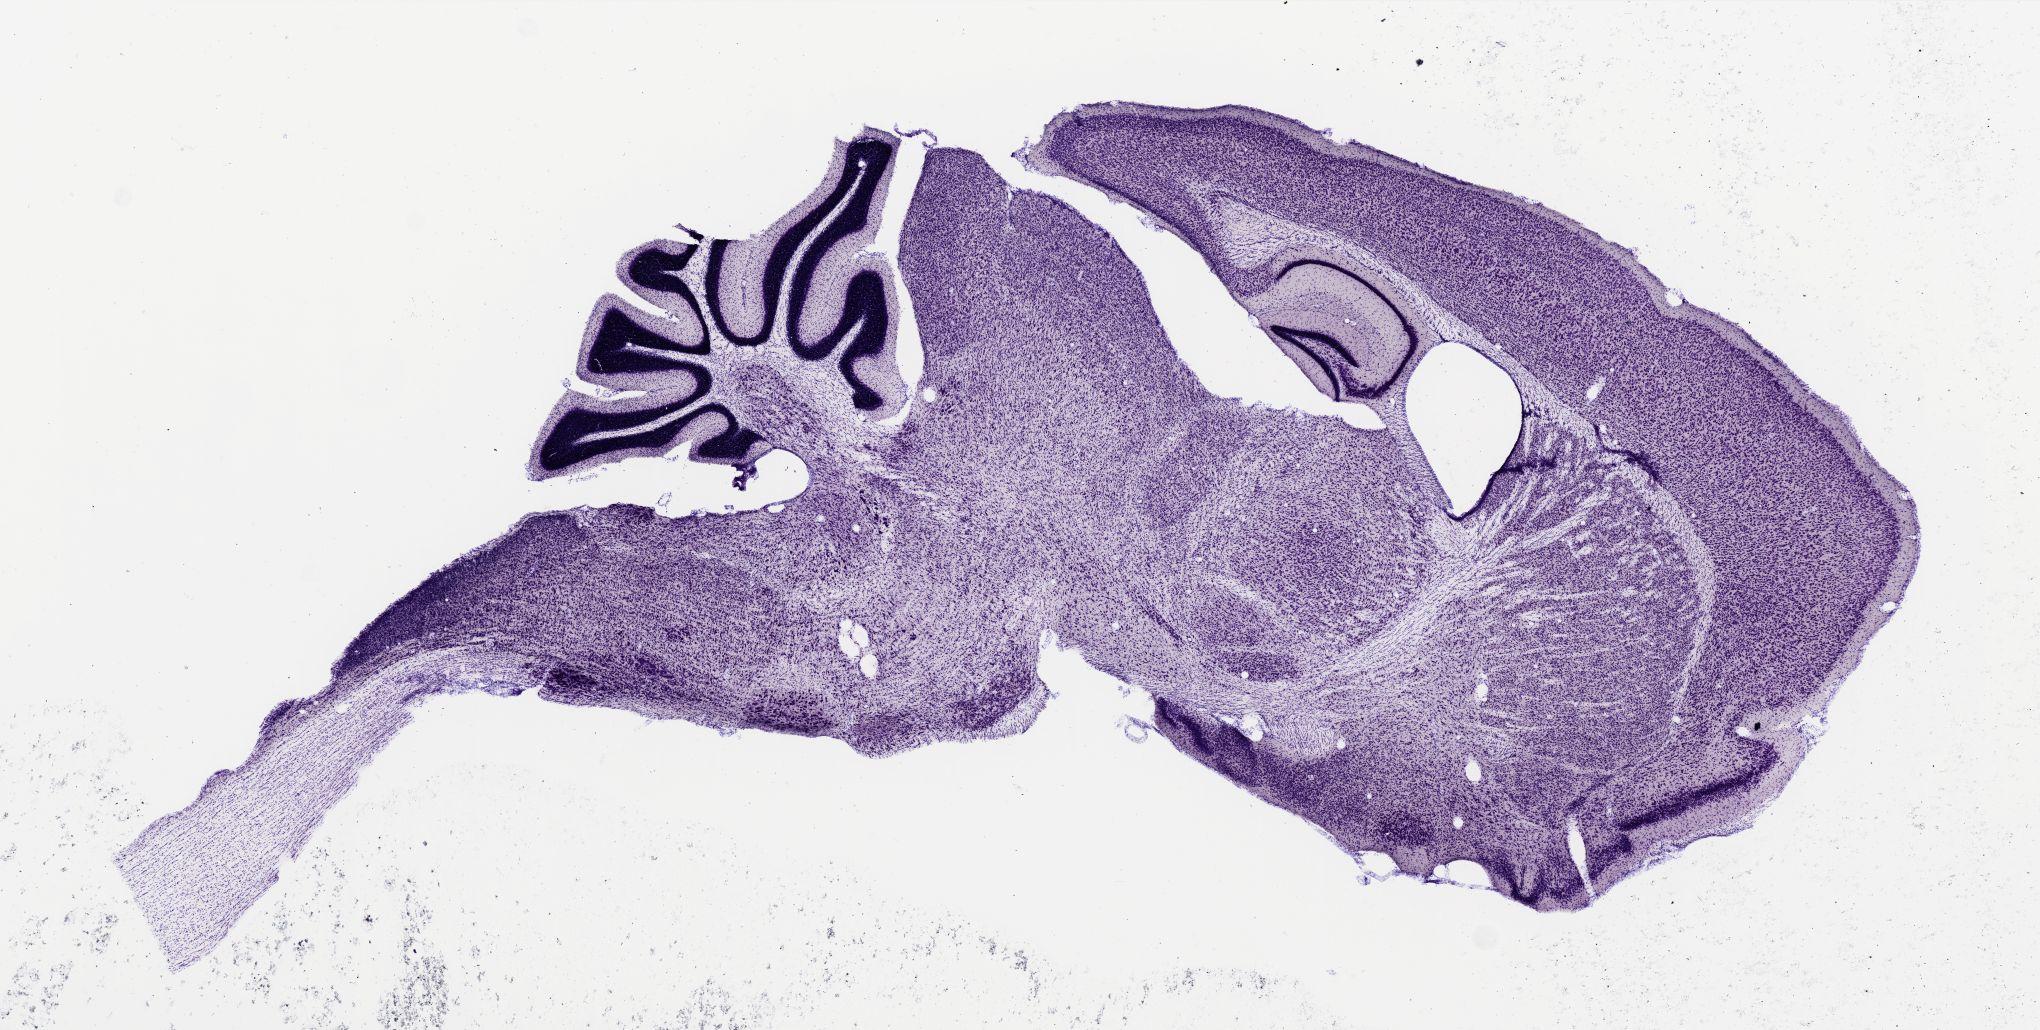

Datasets -> Mus Musculus -> Nissl, sagittal, histo, Whole-Brain, adult

[ Metadata ]   ·   Source: Shawn Mikula

thumbnail

m07b